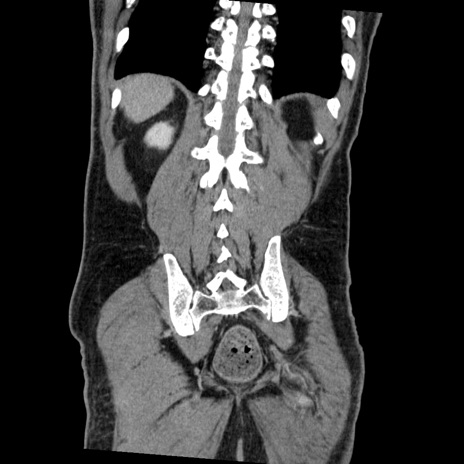

症例22(冠状断像)

【症例】50歳代男性

【主訴】腹痛

【現病歴】AVMからの被殻出血のため回復期リハ病棟入院中。 本日午後3時頃急に下腹部痛が出現した。

【身体所見】意識晴明、左半身不全麻痺、会話の理解は良好、36.5°C、腹部:膨隆、全体に板状硬、下腹部正中に圧痛点あり、反跳痛-、筋性防御不明、右下腹部にope scar